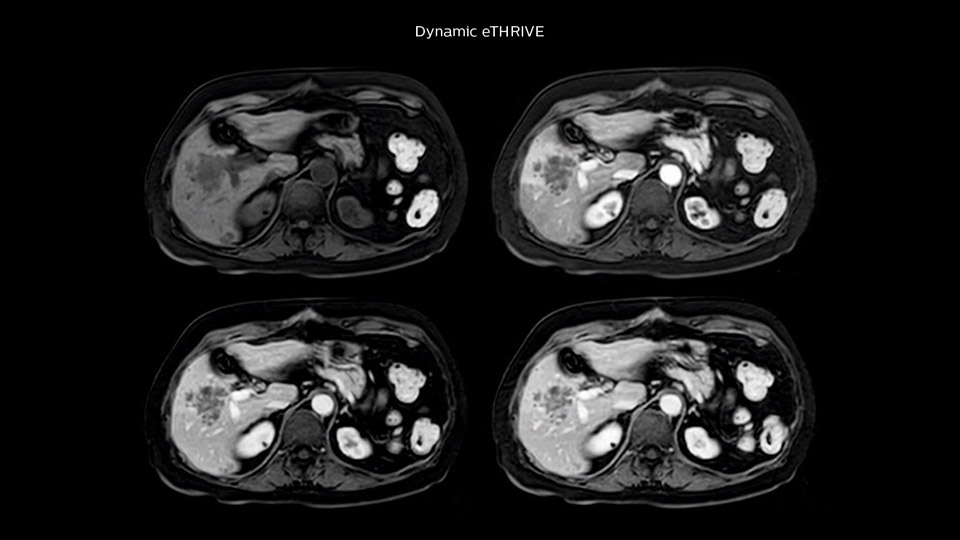

“Our liver exams are quite fast,” says Dr. Baumann. “If the patient tolerates it, we use an arms-up position to reduce the FOV and speed up the exam with dS SENSE.” “We acquire one transversal high resolution T2-weighted sequence with 3 mm slice thickness, for example for pancreas or liver lesions. Then we also add a T2 fat suppressed MultiVane XD SPIR sequence. We perform these two routinely in our liver imaging. We use high dS SENSE factors to significantly shorten scan times to 2-4 minutes, which can improve our protocol; it’s a very robust scan.” “We include mDIXON for the dynamic sequences because of the robust and homogeneous fat suppression we get with that. We had been using eTHRIVE, but we are now quite happy with mDIXON. Sometimes we use a medication to calm the bowels, to further improve the image quality.”

Dr. Baumann then implemented MultiVane XD for motion correction. It uses an extended reconstruction algorithm for imaging that is virtually motion free. “With MultiVane XD we get excellent motion-corrected images with high spatial resolution. We typically first optimize our scan for high image quality, and when satisfied with that, we try to reduce the scan time. So, we combined MultiVane XD with dS SENSE, which allows us to shorten the scan time,” he explains. “The performance of MultiVane XD in liver imaging is outstanding. MultiVane XD with dS SENSE is a powerful development in improving liver image quality.” “As we use breathhold imaging for T2-weighted liver scans, we depend on the patient’s ability to cooperate with the exam. This can present a real challenge when we are looking for small lesions, such as in our oncological patients. However, with MultiVane XD motion correction, we get excellent images. This is important for our surgeons, because they want to know exactly where the lesions are.”